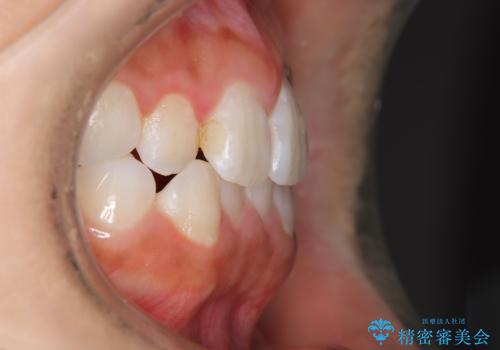

- 子供のころに矯正治療をされていたが、後戻りをしてしまったという20代女性の患者様です。上顎左右の2番が、咬合時に下顎の歯よりも内側に入っているクロスバイトという状態でした。奥歯の咬合関係は変えずに、マウスピース矯正にて前歯の並びを綺麗なアーチに仕上げました。再度後戻りしてしまうリスクを軽減させるために、リテーナー(保定装置)をお渡ししています。